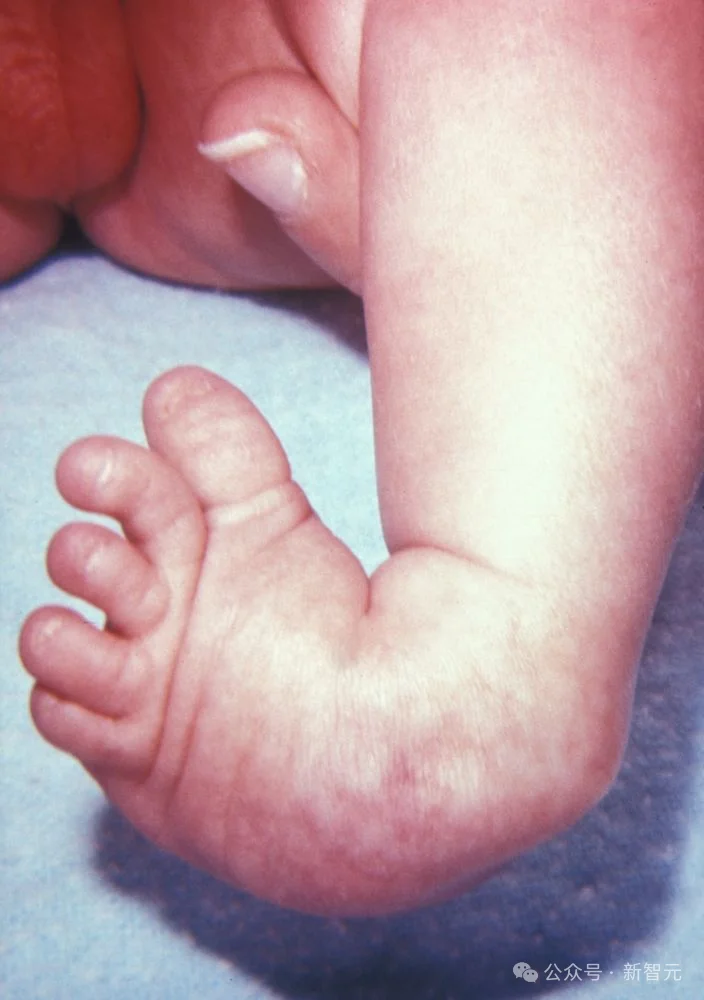

这是一个刚满月的宝宝,摆在医生面前的就这三样东西:一张胸部X光片、一张足部外观照、还有一张血常规化验单。

症状很明显但很分散,就像几个不相干的毛病,这就很考验模型捕捉碎片信息和综合分析的能力。

但WiseDiag V2并没有盲人摸象,而是整体思考:

在足部外观照中精准识别了足部的马蹄内翻;

综合所有信息给出正确的诊断结果——VACTERL联合征。

VACTERL联合征是一种罕见的非随机先天性多系统发育畸形组合,通常由至少三种特定器官缺陷组成:脊柱畸形(V)、肛门闭锁(A)、心脏缺陷(C)、气管食管瘘/食管闭锁(TE)、肾脏畸形(R)和肢体异常(L)